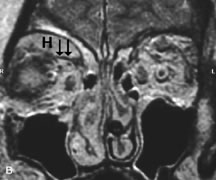

Breast carcinoma metastatic to the orbit has been demonstrated to be hypointense to the surrounding orbital fat on T1-weighted studies and hyperintense on T2-weighted images and has an affinity to the extraocular muscles (Fig. 20).50,64 The MRI characteristics of prostate carcinoma metastatic to the orbit have been described as involving the greater and lesser wing of the sphenoid, orbital roof, and optic canal. Diffuse bone hypertrophy with isointense or slightly hyperintense tissue on T1-weighted images represents the osteoblastic carcinomatous bone infiltration. Contrast enhancement is variable on T1-weighted and fat-suppressed images.65

Fig. 20. A. T1-weighted MR scan demonstrates nodular enlargement of both medial rectus muscles (arrows). B. T1-weighted fat-suppressed contrast-enhanced scan confirms the presence of small metnstatic deposits within the muscles (open arrows).